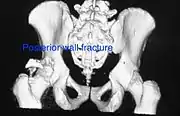

Posterior wall fracture as seen on 3-D CT scan

Posterior column and wall fracture as seen on 3D CT